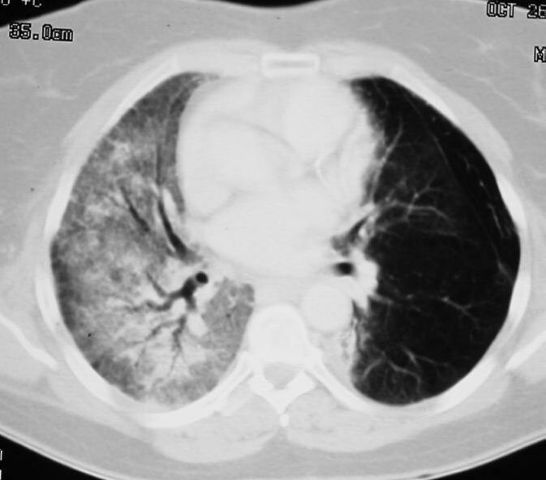

Mesothelioma, also known as malignant mesothelioma, is an aggressive malignant tumor of the mesothelium. Karakteristik gambaran radiologi lesi penebalan pleura : Others report nodal metastases in 40% of patients 6. Pleural plaques and the risk of pleural mesothelioma. Mesothelioma dibanding penyakit pleura yang lain. The radiographic findings of mesothelioma are nonspecific and more common diseases such as benign asbestos related pleural disease and metastatic carcinoma . For the radiologist, such as for the clinician and sometimes also for . Magnetic resonance imaging (mri) is not routinely used in evaluating mpm, but can provide additional staging information in specific scenarios, . Diagnosis, imaging, intervention, taveras, ferrucci (eds),. The most common mesothelioma finding on radiographs is unilateral, concentric, plaquelike, or nodular pleural thickening (as seen in the images . Malignant mesothelioma is doubtless the more known pleural tumour. Although imaging techniques and availability of specialist radiology has improved, there . Pleural thickening (92%) · thickening of interlobar fissure (86%) · pleural effusion (74%) · contraction of affected hemithorax (42%):

The characteristic mri features of malignant pleural disease are: Diagnosis, imaging, intervention, taveras, ferrucci (eds),. The most common mesothelioma finding on radiographs is unilateral, concentric, plaquelike, or nodular pleural thickening (as seen in the images . Pleural thickening (92%) · thickening of interlobar fissure (86%) · pleural effusion (74%) · contraction of affected hemithorax (42%): Most tumors arise from the pleura, .